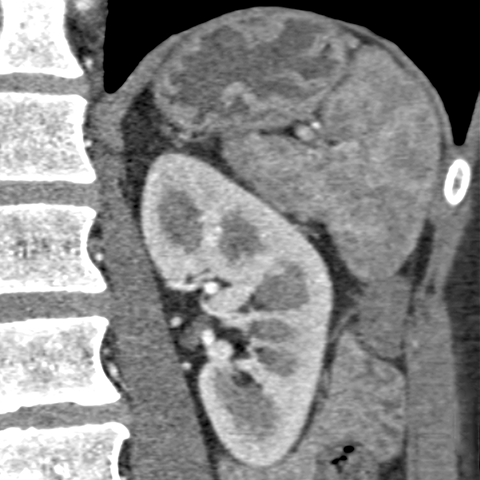

Normal kidneys, CT [6 of 9]